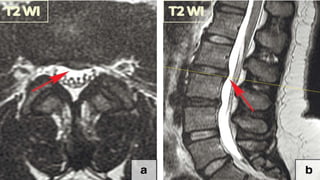

Ligamentum flavum hypertrophy

• It extends from the 2nd vertebra to the 1st sacral

vertebra, connecting the two adjacent laminae

• The ligamentum flavum tends to become

hypertrophic with the degeneration of the elastic

fibres and the proliferation of type II collagen.

• Abnormal motions and instability within the

involved segments are potential aetiologies of

ligamentum flavum hypertrophy as the body tries

to stabilise the diseased segment by making it

• Surgical removal is the only

therapeutic manoeuvre for

patients with symptoms caused

by ligamentum flavum

hypertrophy (Fig. 26b, c).